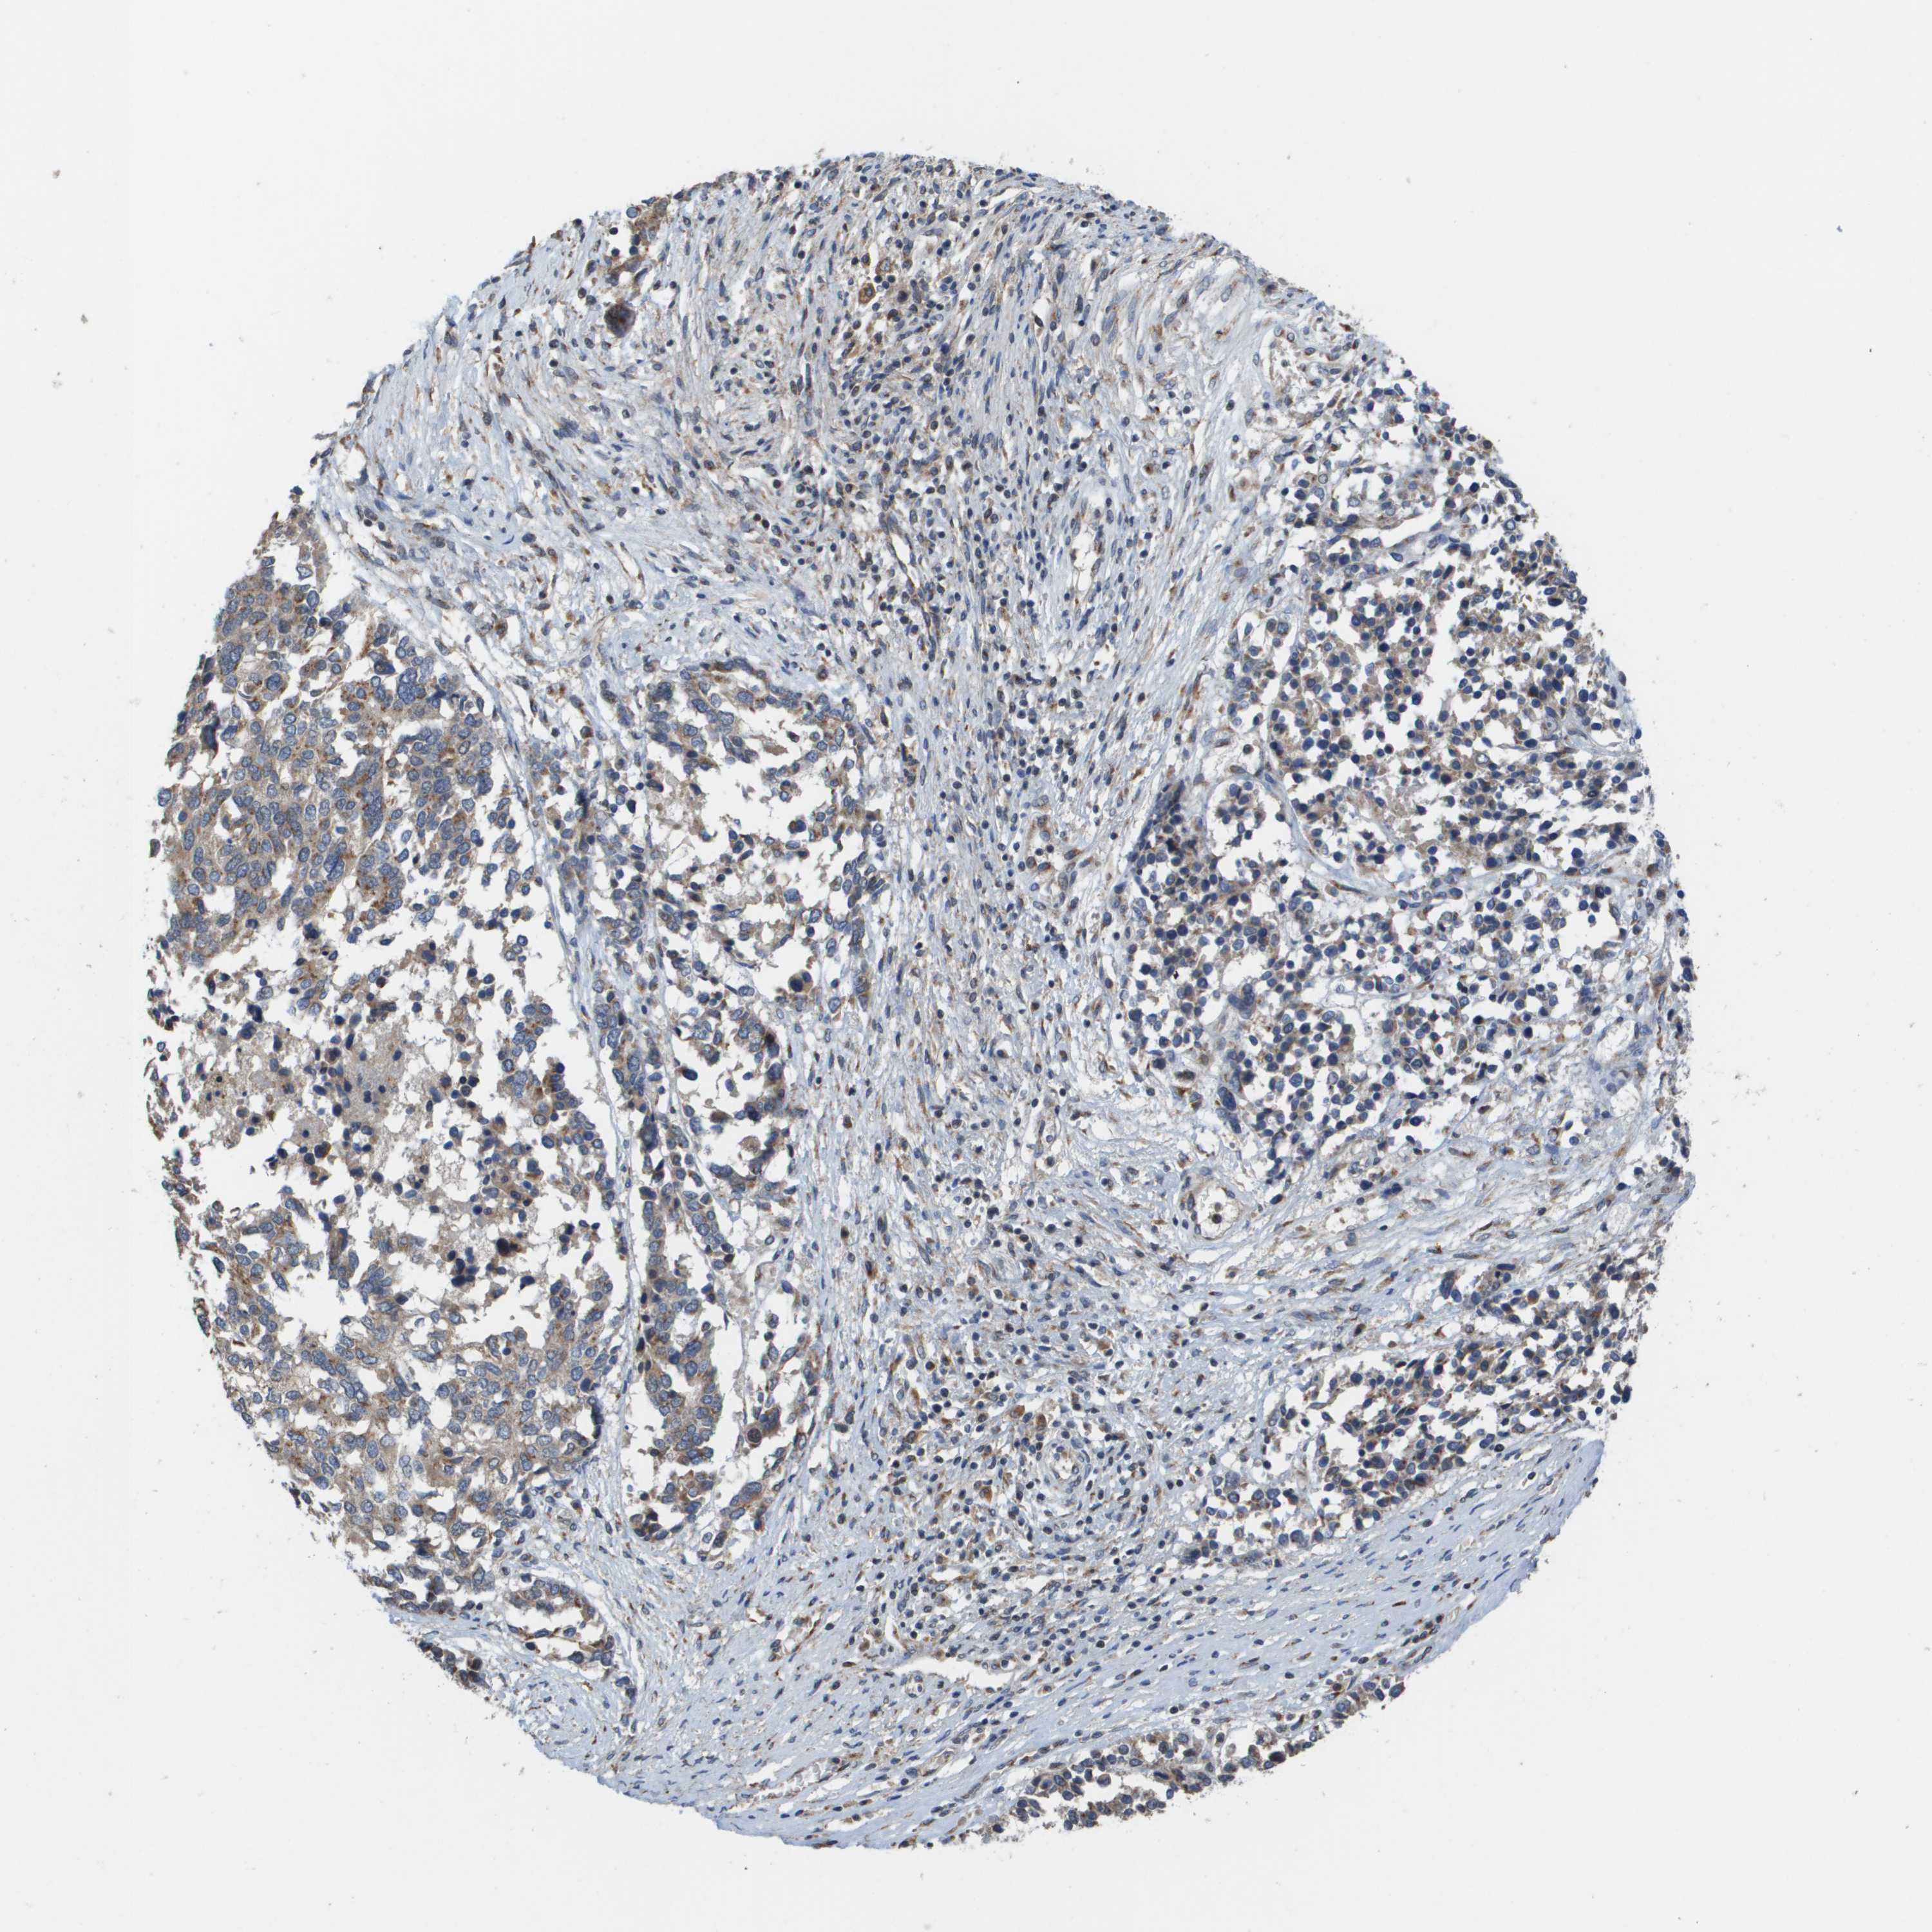

OVARIAN CANCER - Protein expressioni

A mouse-over function shows sample information and annotation data. Click on an image to view it in a full screen mode. Samples can be filtered based on level of antibody staining by selecting one or several of the following categories: high, medium, low and not detected. The assay and annotation is described here.

Note that samples used for immunohistochemistry by the Human Protein Atlas do not correspond to samples in the TCGA dataset.

Antibody stainingi

Antibody staining in the annotated cell types in the current human tissue is reported as not detected, low, medium, or high, based on conventional immunohistochemistry profiling in selected tissues. This score is based on the combination of the staining intensity and fraction of stained cells.

Each image is clickable and will lead to virtual microscopy that enables deeper exploration of all samples and also displays staining intensity scores, fraction scores and subcellular localization as well as patient and tissue information for each sample.

Staining

High

Medium

Low

Not detected

Carcinoma, NOS

Cystadenocarcinoma, serous, NOS